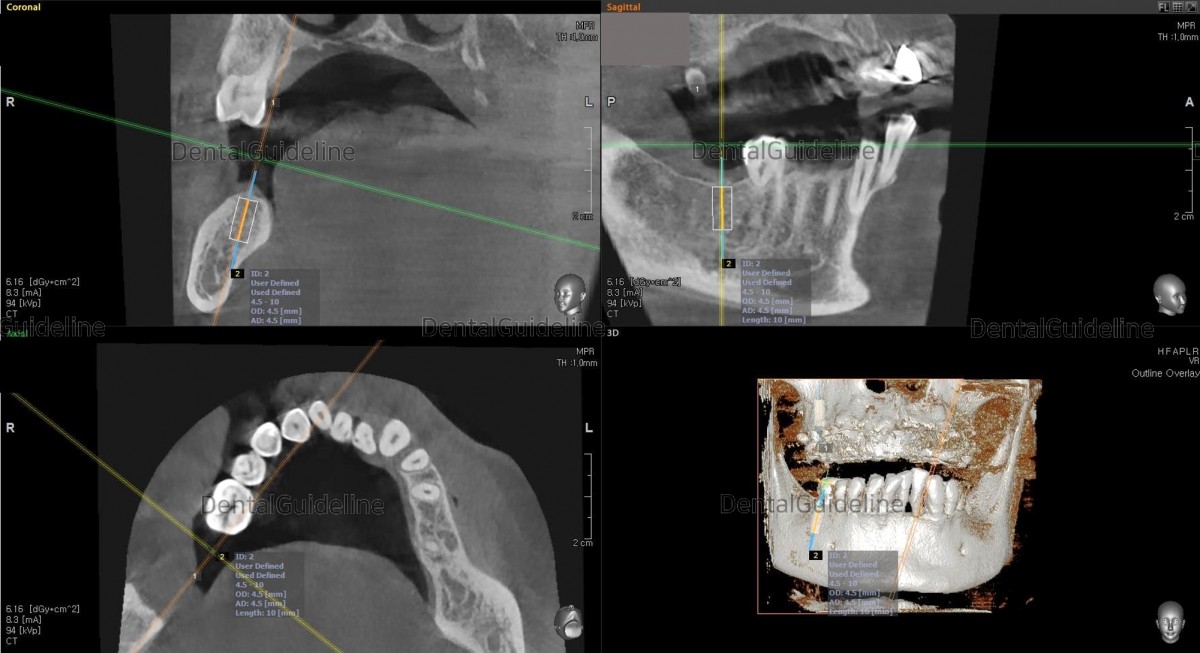

- implant surgery was simply simulated on the CBCT scanned image.

- post-op CBCT.